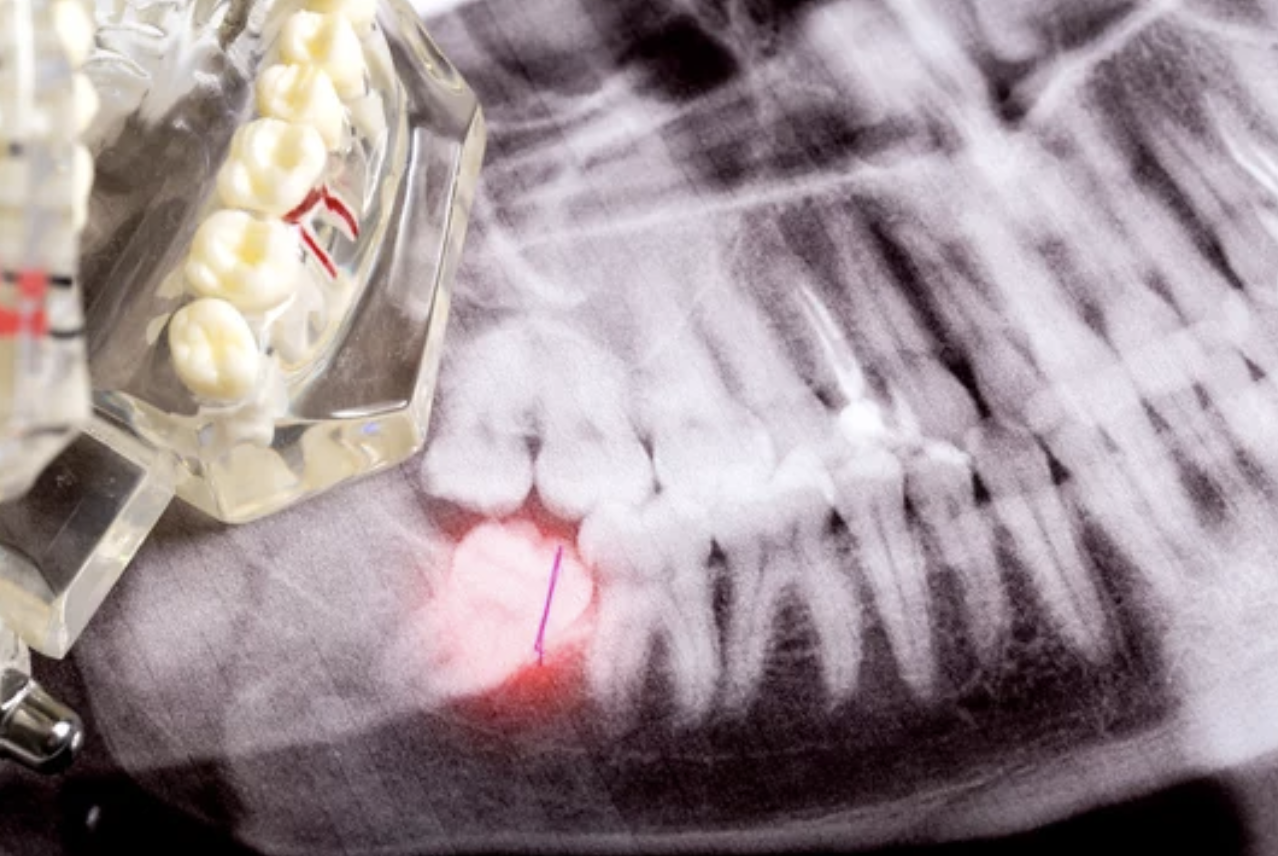

Q親知らずが生えてきました。抜いた方がいいですか?

親知らずはむし歯や歯周病のリスクが高く、歯並びやかみ合わせに悪影響を及ぼすことがあります。

ただし、状態や生え方によって対応は異なるため、レントゲンなどで確認したうえでの判断が必要です。まずは一度ご相談ください。 -